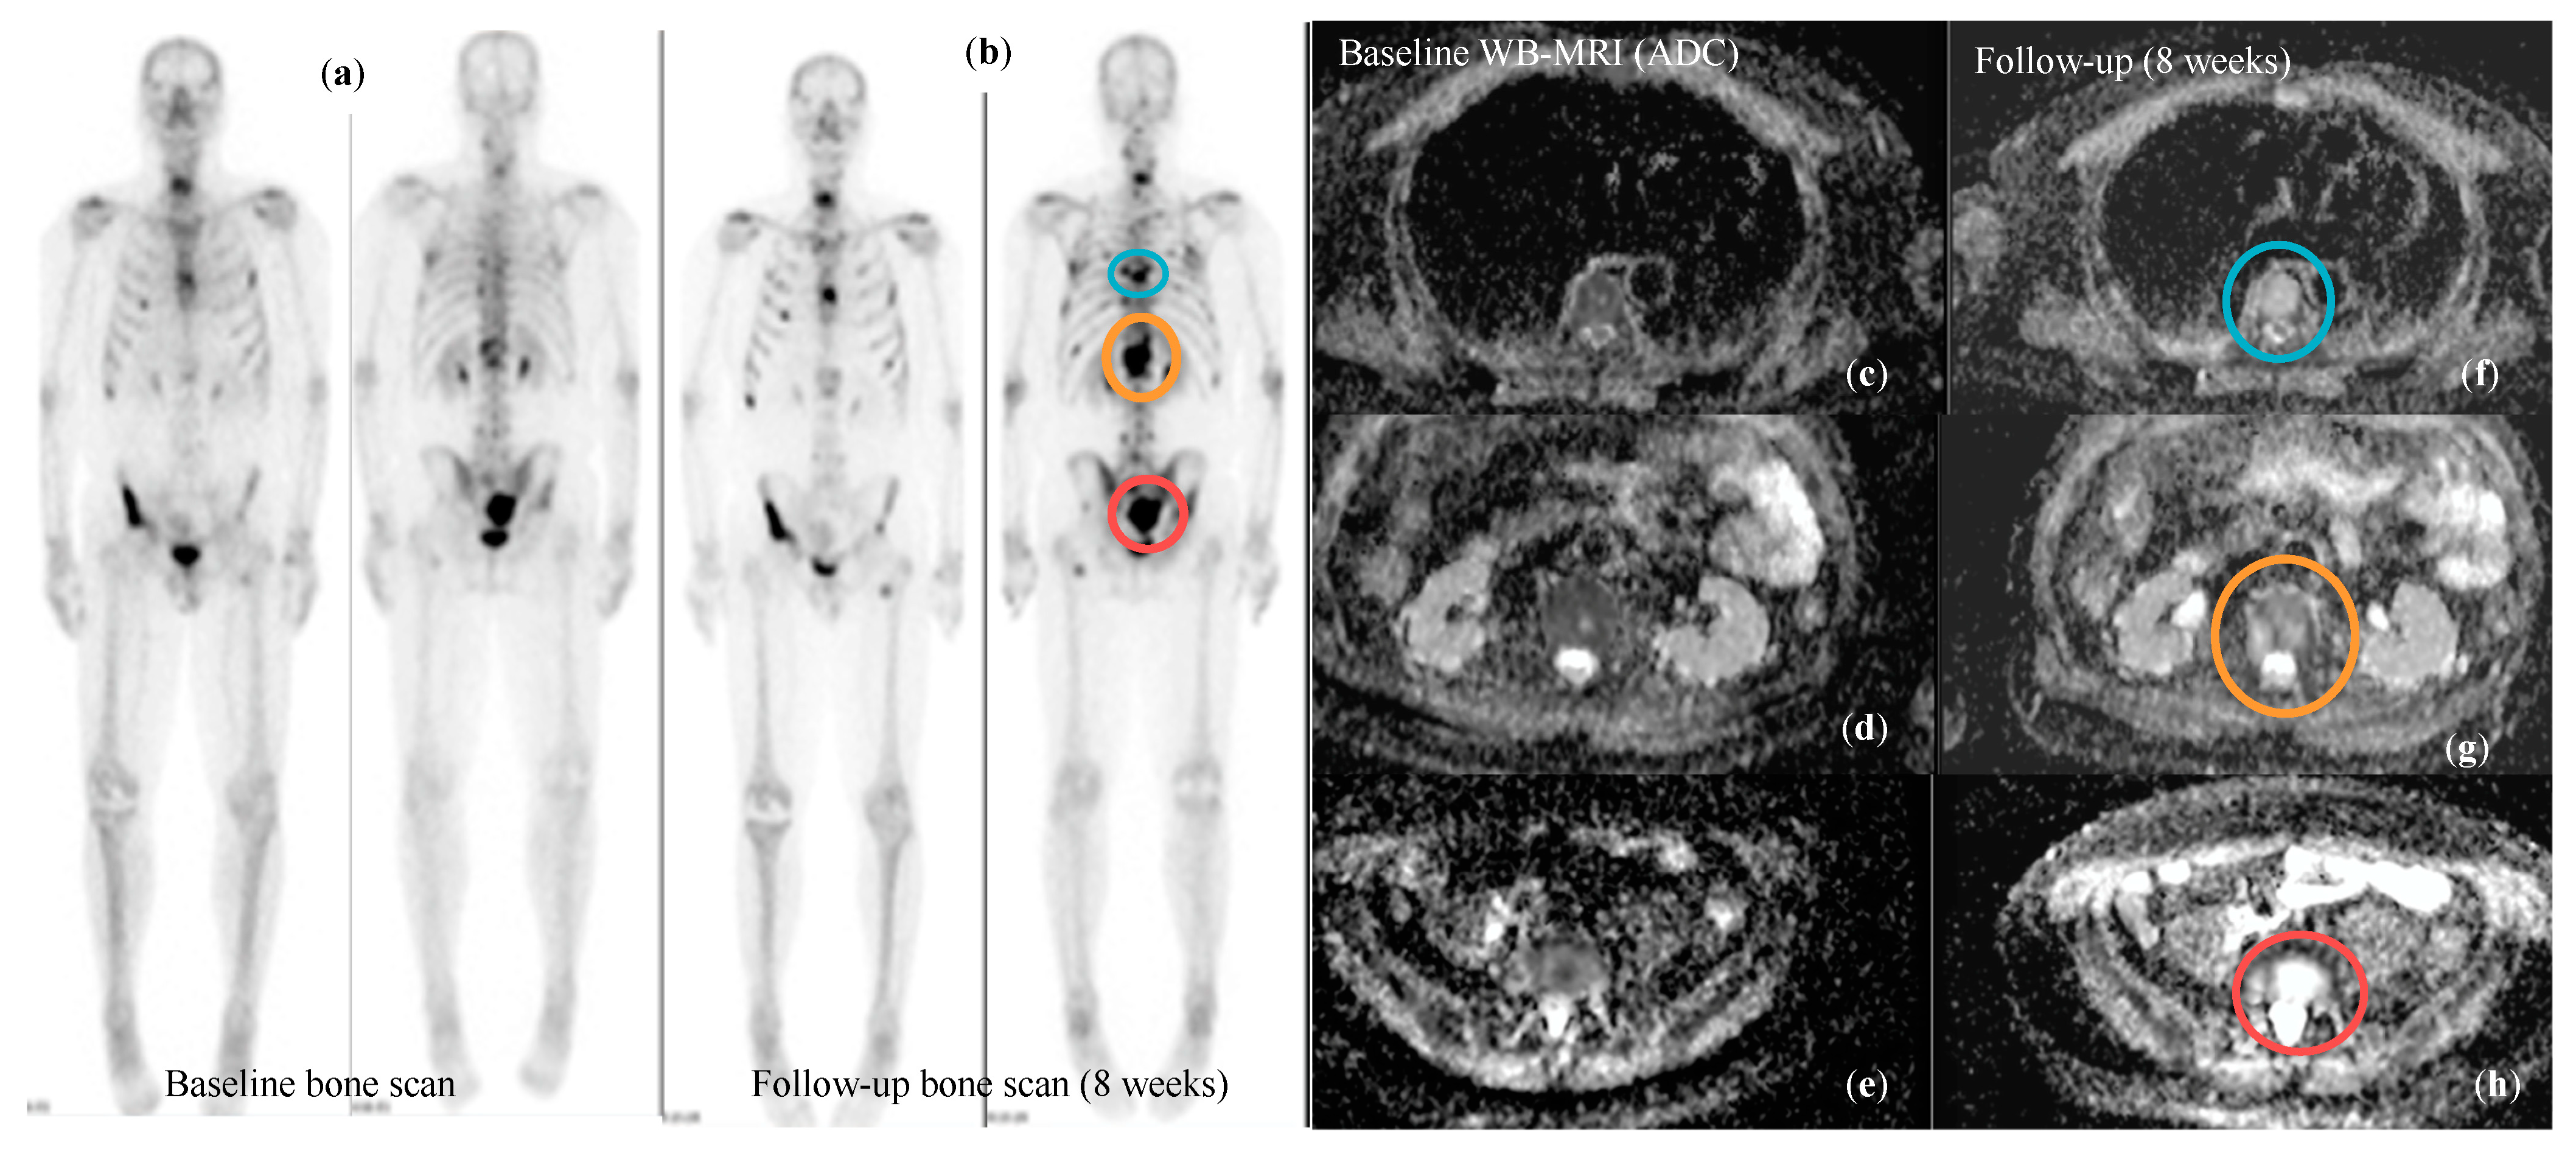

3.5. Response Assessment in Metastatic Prostate Cancer

| Messiou et al. Eur Radiol 2011 [102] | Diffusion Weighted MRI | Overall ADC of bone lesions increases both in responders and progressors, but the magnitude of increase if higher for responders. An increase in overall ADC > 25% is 75% sensitive and 66.6% specific for response. ADC alone cannot confidently assess response or progression as the changes in bone marrow composition significantly influence ADC values. | |